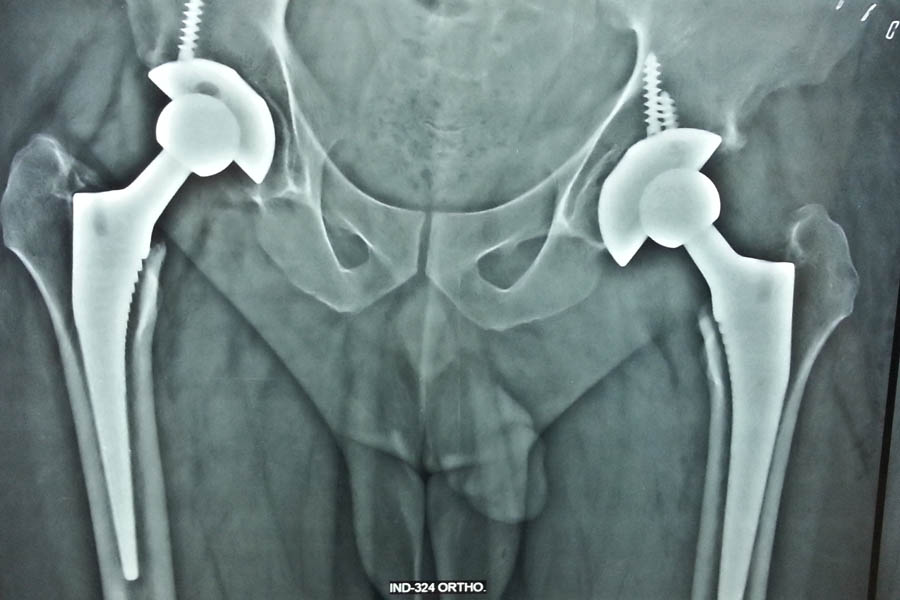

Total Hip Replacement

Case 1